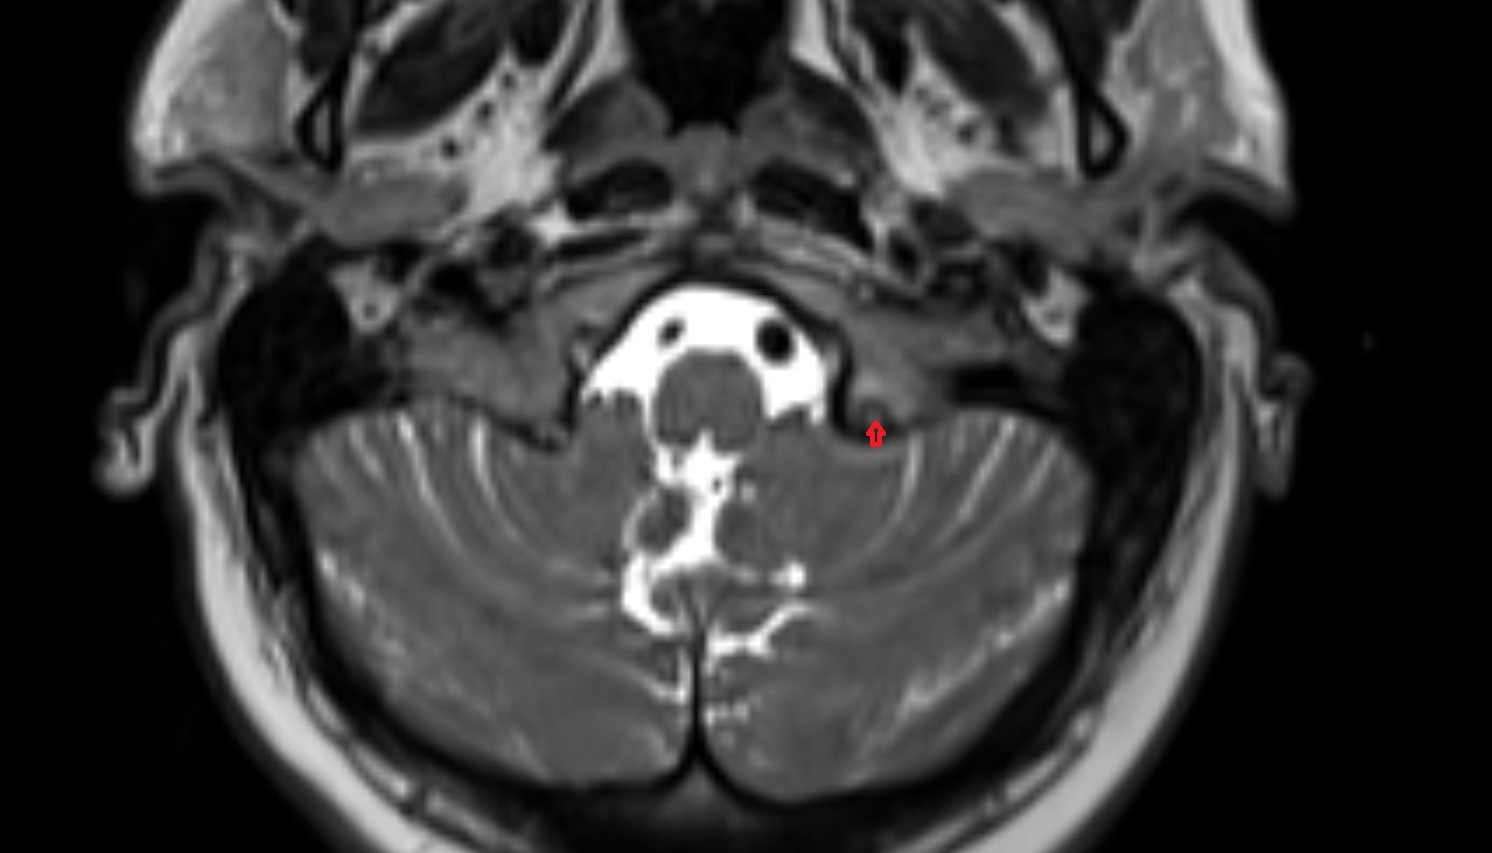

- Cerebellopontine cistern

- Lateral aperture of fourth ventricle (foramen of Luschka)